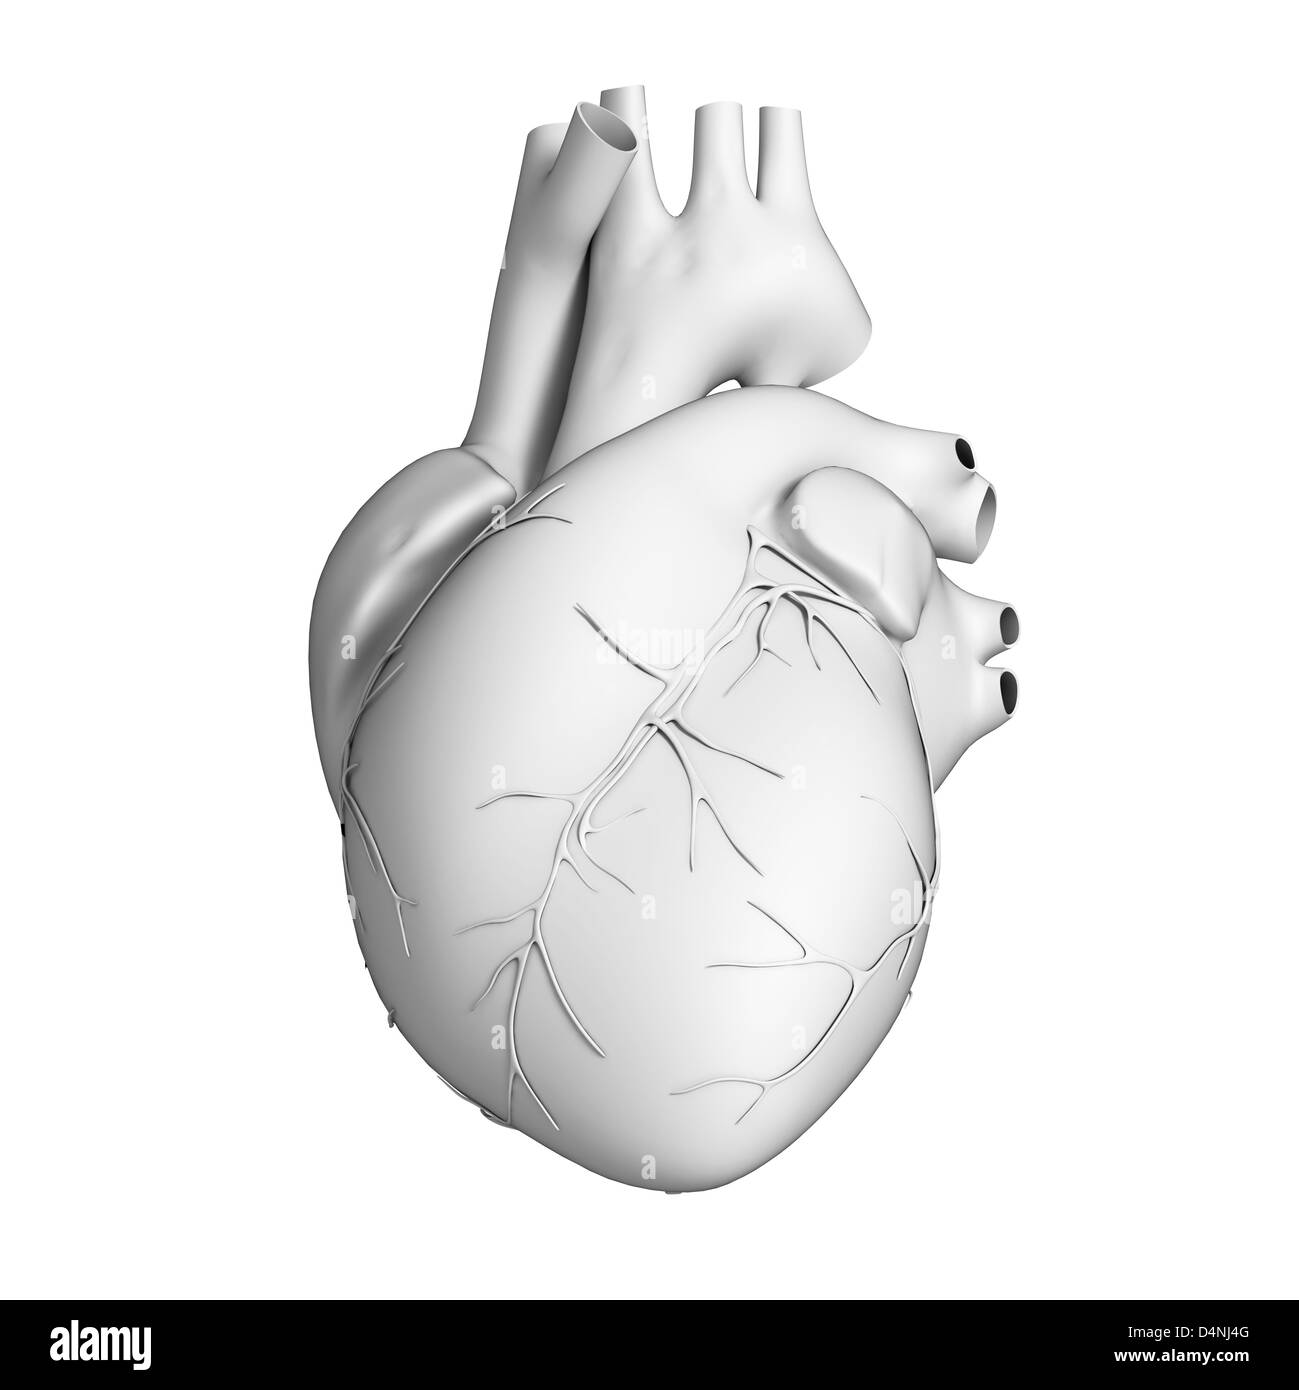

White heart Stock Photohttps://www.alamy.com/image-license-details/?v=1https://www.alamy.com/stock-photo-white-heart-54564957.html

White heart Stock Photohttps://www.alamy.com/image-license-details/?v=1https://www.alamy.com/stock-photo-white-heart-54564957.htmlRMD4NJ4D–White heart

White heart Stock Photohttps://www.alamy.com/image-license-details/?v=1https://www.alamy.com/stock-photo-white-heart-54564962.html

White heart Stock Photohttps://www.alamy.com/image-license-details/?v=1https://www.alamy.com/stock-photo-white-heart-54564962.htmlRMD4NJ4J–White heart

White heart Stock Photohttps://www.alamy.com/image-license-details/?v=1https://www.alamy.com/stock-photo-white-heart-54564960.html

White heart Stock Photohttps://www.alamy.com/image-license-details/?v=1https://www.alamy.com/stock-photo-white-heart-54564960.htmlRMD4NJ4G–White heart